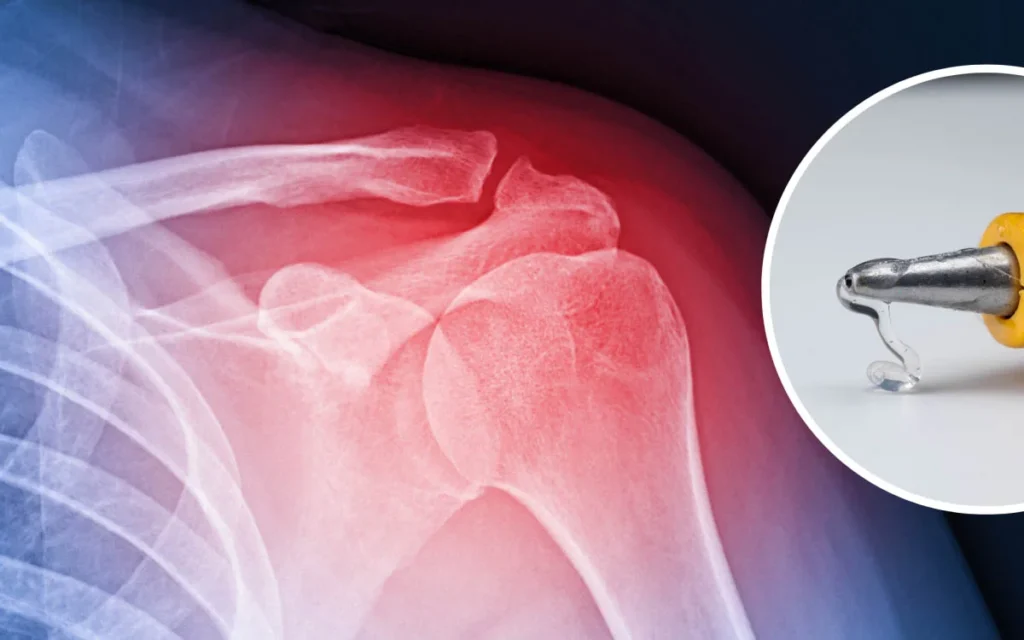

मानव सभ्यता का एक लंबा सफर रहा है। विज्ञान और तकनीक ने हमेशा जीवन को सरल बनाने का काम किया है। चिकित्सा विज्ञान ने तो कई असंभव लगने वाली बीमारियों का इलाज संभव कर दिखाया है। कभी हड्डी टूटना, जिसे फ्रैक्चर कहते हैं, एक बड़ी समस्या थी। महीनों तक आराम करना पड़ता था। बार-बार डॉक्टर के पास जाना पड़ता था। इलाज लंबा चलता था। लेकिन अब चीन के वैज्ञानिकों ने एक कमाल का आविष्कार किया है। यह चिकित्सा क्षेत्र में बड़ा बदलाव ला सकता है। इसका नाम है ‘बोन ग्लू’ (Bone Glue)। यह टूटी हुई हड्डियों को मात्र तीन मिनट में जोड़ सकता है।

हड्डी टूटना कोई नई बात नहीं है। सड़क दुर्घटनाएं, खेल के दौरान चोट लगना, ऊंचाई से गिरना, या बुढ़ापे में हड्डियों का कमजोर होना, जिसे ऑस्टियोपोरोसिस कहते हैं, ये सब फ्रैक्चर के कारण हैं। पहले टूटी हड्डी को जोड़ने के लिए प्लास्टर का इस्तेमाल होता था। कई बार स्क्रू, स्टील प्लेट या रॉड की जरूरत पड़ती थी। कुछ मामलों में शरीर में इंप्लांट लगाना पड़ता था। ये इंप्लांट शरीर में लंबे समय तक रहते थे। अक्सर इन्हें निकालने के लिए दोबारा सर्जरी करनी पड़ती थी। हड्डी को पूरी तरह ठीक होने में कई महीने लग जाते थे। इस दौरान मरीज को अपना काम छोड़ना पड़ता था। उनकी रोजमर्रा की जिंदगी प्रभावित होती थी।

पूर्वी चीन के झेजियांग प्रांत में डॉ. लिन जियानफेंग और उनकी टीम ने एक खास ‘बोन ग्लू’ बनाया है। उन्होंने इसे ‘बोन 02’ नाम दिया है। इस ग्लू का विचार उन्हें समुद्र में रहने वाले सीप (mussels) से मिला। सीप पानी के नीचे चट्टानों से बहुत मजबूती से चिपके रहते हैं। इसी प्राकृतिक सिद्धांत का उपयोग करके यह ‘बोन ग्लू’ बनाया गया है।

यह एक खास तरह का रासायनिक और जैविक मिश्रण है। यह हड्डियों की सतह पर बहुत जल्दी चिपक जाता है। यह सिर्फ दो से तीन मिनट में टूटी हड्डियों को जोड़ देता है। सबसे अच्छी बात यह है कि अगर खून बह रहा हो, तब भी यह काम करता है। जब हड्डी पूरी तरह ठीक हो जाती है, तो यह ग्लू अपने आप शरीर में घुल जाता है। इसका मतलब है कि मरीज को इंप्लांट निकालने के लिए दूसरी सर्जरी नहीं करवानी पड़ेगी।

अब तक 150 से अधिक मरीजों पर इसका सफल परीक्षण हो चुका है। जब इस ग्लू से जुड़ी हड्डी पर 400 पाउंड से भी ज्यादा वजन डाला गया, तब भी हड्डी मजबूती से जुड़ी रही। यह तकनीक सुरक्षा और असर, दोनों मामलों में सफल साबित हुई है।